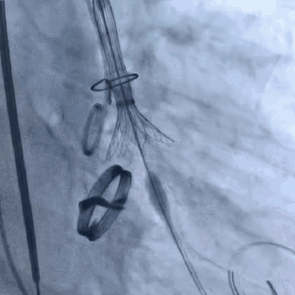

3. 术中实行的20球囊的预扩,AV26瓣膜的释放,瓣膜释放后发现还有展开的余地,故进一步选择23的球囊进行后扩使人工瓣膜更贴合主动脉根部结构。

4. 根据术前CT评估,跨瓣角度为LAO 12° CAU 5°(右窦中心位)左右,球囊预扩角度为LAO 32° CRA 2°(左冠切线位)左右,释放角度为RAO 16° CAU 24°(左右重合)左右。使用20mm球囊预扩,根据沛嘉TaurusOne®产品设计特点采取瓣环平面下2-4mm高度释放策略。

20mm球囊预扩张

瓣膜缓慢释放

23mm球囊后扩张